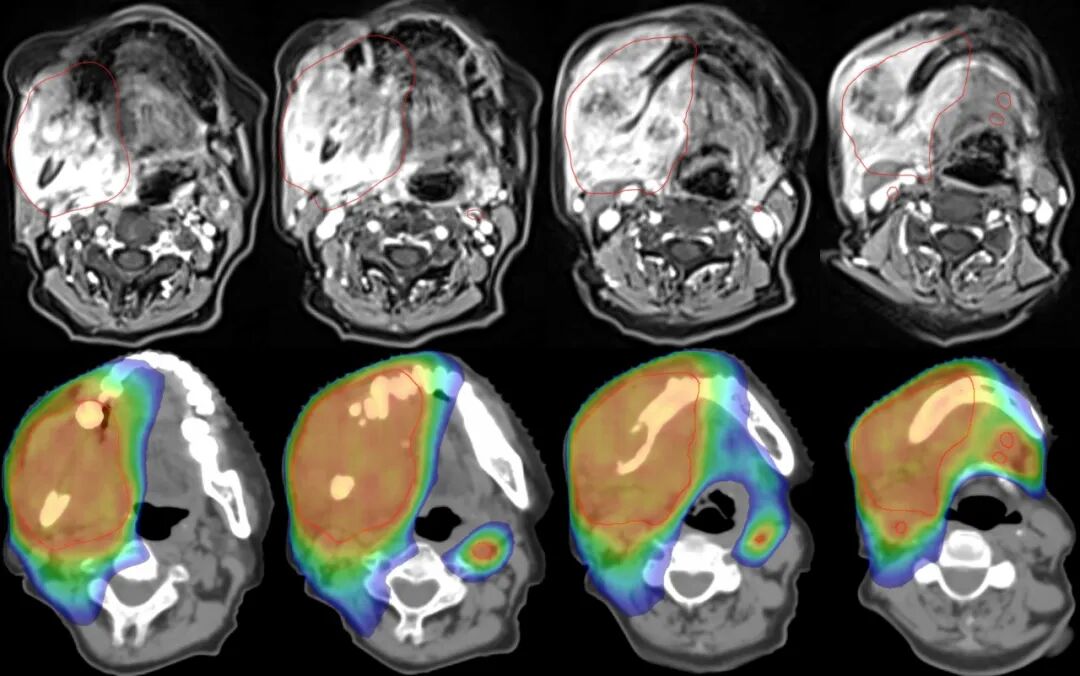

圖注:上排紅線內(nèi)為腫瘤照射靶區(qū)。下排為劑量分布圖,可見中心區(qū)高劑量照射,周邊劑量快速跌落,形成銳利的集束聚焦照射,周圍重要器官得到良好保護。